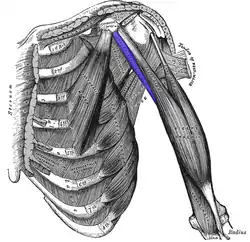

Deep muscles of the chest and front of the arm, with the boundaries of the axilla. Coracobrachialis is shown in blue. | |